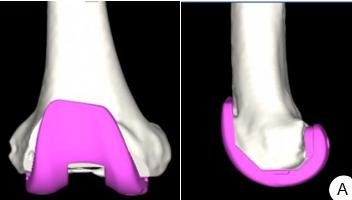

Non-infectious knee prosthesis loosening treated by revision with Sleeve extension rod combined with MBT prosthesis under the aid of pre-operative planning

Cao Xun, Zheng Shanbin, Sun Jiahao, Chen Zhiyuan, Zhu Jiaqing, Ma Bowen, Xia Tianwei, Zhang Chao, Shen Jirong

BACKGROUND: With the widespread application of total knee arthroplasty in China, non-infectious prosthesis loosening has become one of the main reasons for postoperative revision. For complex loosening cases, traditional revision techniques are relatively complex and difficult. The application of artificial intelligence-assisted preoperative planning combined with Sleeve extension rods and mobile bearing tray prostheses provides a new solution for precisely reconstructing joint stability and mechanical alignment, which is expected to improve the long-term outcomes of revision surgeries.

OBJECTIVE: To explore the mid-and early-term clinical efficacy of revision surgery for non-infectious total knee prosthesis loosening using Sleeve extension rods combined with mobile bearing tray prostheses under the assistance of artificial intelligence-assisted preoperative planning.

METHODS: A retrospective analysis was conducted on 17 patients with non-infectious prosthesis loosening after total knee arthroplasty in Department of Orthopedics and Traumatology, Jiangsu Provincial Hospital of Traditional Chinese Medicine from January 2021 to September 2024. There were 6 males and 11 females, aged from 59 to 81 years old, with an average age of (72.06±6.10) years. There were 8 cases on the left side and 9 cases on the right side. The service life of the prosthesis ranged from 2 to 22 years, with an average of (10.53±4.60) years. All cases were revisions after primary replacement. The reasons for revision included periprosthetic osteolysis with liner wear in 15 cases, old femoral condyle fracture leading to prosthesis loosening in 1 case, and tibial plateau prosthesis fracture in 1 case. Among them, 13 cases were of AORI type IIB and 4 cases were of AORI type IIA. The prosthesis models designed by artificial intelligence before surgery were recorded and compared with the models actually used during surgery. The visual analog scale scores, American Knee Society knee scores, knee hip-knee-ankle angles, and knee joint ranges of motion of the patients before surgery, 1 week, 6, and 12 months after surgery were compared and the surgical efficacy was assessed.

RESULTS AND CONCLUSION: (1) Except for 1 case with poor wound healing 1 month after surgery, the rest of the patients recovered well without adverse events such as deep vein thrombosis of the lower extremities, infection, periprosthetic fracture, and prosthesis loosening. (2) The follow-up time ranged from 6 to 41 months, with an average of (23.63±12.50) months. At the last follow-up, two patients had slight soreness and discomfort after activity, and one patient had obvious pain during activity. (3) After revision treatment, the visual analog scale pain scores of the patients, rest pain, exercise pain, the range of motion of the affected side, hip-knee-ankle angle, and American Knee Society knee score were significantly improved (P < 0.01), with statistically significant differences. (4) The matching rate of the femoral condyle and tibial plateau prostheses designed by artificial intelligence pre-operatively was 85%; the matching rate of the remaining components was 62%. (5) It is concluded that the use of Sleeve extension rods combined with mobile bearing tray prostheses for non-infectious knee revision surgery can effectively correct the joint alignment, fill bone defects, relieve pain, improve the range of motion of the knee joint, and enhance the quality of life of patients with severe bone defects. The mid-and early-term postoperative efficacy is good. Artificial intelligence-assisted preoperative planning can help improve surgical accuracy, reduce surgical difficulty, minimize surgical risks, and promote postoperative recovery of patients.

Figures and Tables | References | Related Articles | Metrics